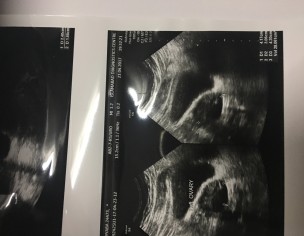

M 32 unmarried. Known case of pcos. Diagnosed with a fibroid in my cervix. Doctor said no for surgery as fibroid is on ovary opening and surgery may lead removal of everything. My problem is heavy bleeding with clots and bleeding within periods. My CA125 CEA thyroid test everything is normal. M obese. Doctor asked me to reduce weight and no medicine is given to me even when my sugar bp levels are fluctuating. Kindly suggest me how can i deal with my fibroid and get rid of this bleeding

Attach Photo here: